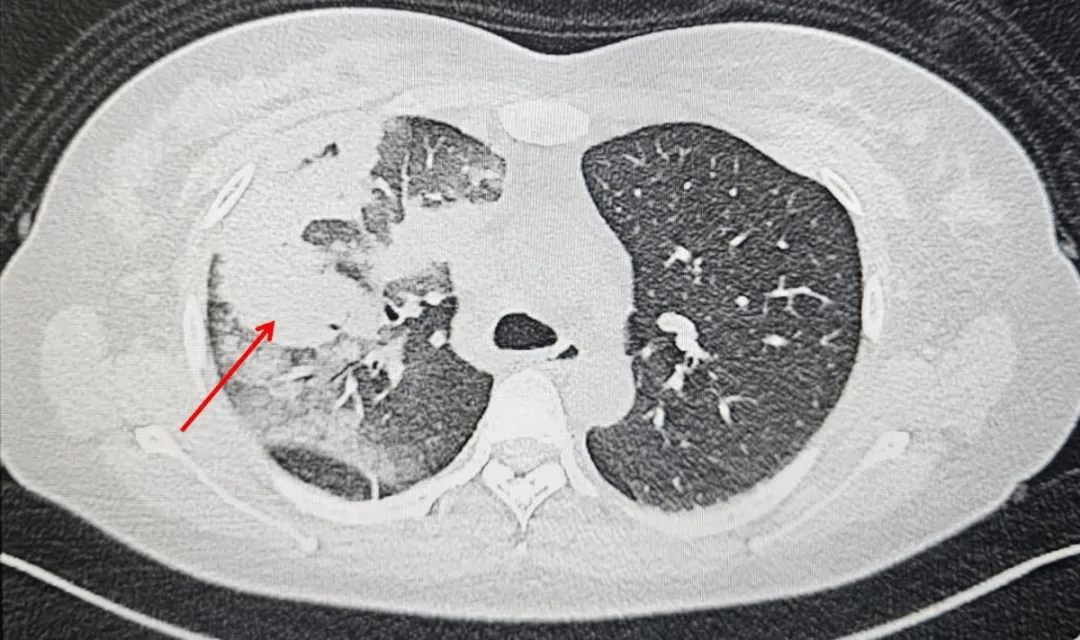

一周前,李女士因无明显诱因出现发热、咳嗽、咳痰,自行服药后症状不见好转,来到西安市第九医院呼吸与危重症医学科就诊。这一查不要紧,胸部CT显示:左肺上叶及中叶多发高密度影! 这样的影像学表现绝非普通感冒那么简单。

入院时胸部CT,左肺上叶及中叶多发高密度影

经过一段时间的规范抗真菌治疗,李女士的病情显著好转,复查胸部CT显示病灶明显吸收。目前李女士已出院,只需口服抗真菌药物并定期来门诊复查即可。